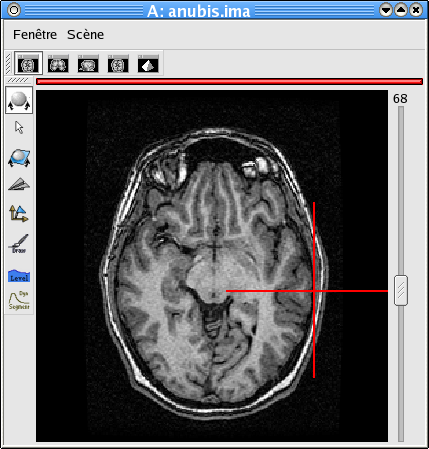

If your image is not spatially normalised, Anatomist will help you to click on the 3 or 4 points of interest.

- If the volume is not already visible, click on the edit button of one of the point parameters to have Anatomist display it

- Set the Anatomist view so as to see the point (use the slice slider) and click in it on the wished point.

- When the cursor position is good, click on the button of the 3D point in BrainVISA: the position is transfered from Anatomist to BrainVISA.

- If you are not happy with the position, you can restart the operation: click again on other points then on the parameter button to validate: a new position replaces the previous one in BrainVisa.

You have to select 3 points (you can use a sagittal slice if you prefer):

- Intersection of anterior commissure with interhemispheric plane;

- Intersection of posterior commissure with interhemispheric plane;

- Any point of the interhemispheric plane not aligned with the previous ones.

Anterior commissure: